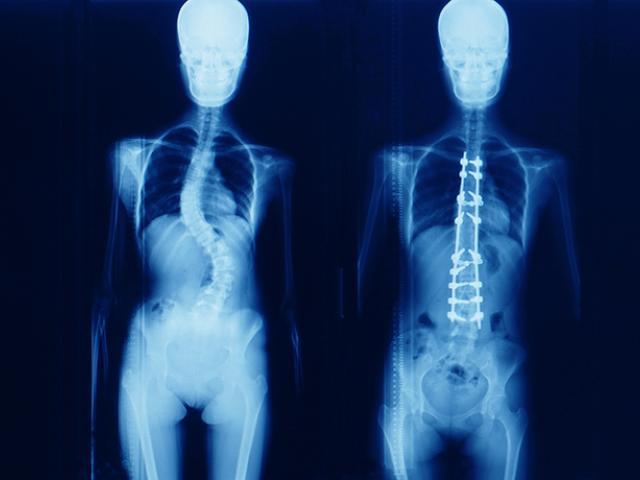

La escoliosis es una curvatura anormal de la columna vertebral hacia un lado y tiene varias causas diferentes.